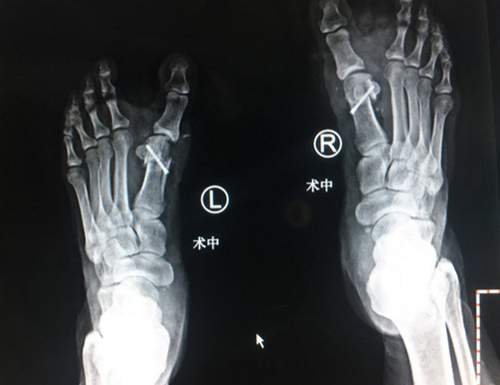

石荣剑院长为李大姐进行了双足踇外翻矫形术。麻醉师采用超声引导下神经阻滞,手术团队采用不到一厘米切口,4毫米进口超声磨锯微创截骨,手术全程无血渗出,完美修整踇外翻。

术中X线

手术很成功,术后第二天几乎就感觉不到疼痛了,术后三天换药基本看不到伤口,李大姐很开心。